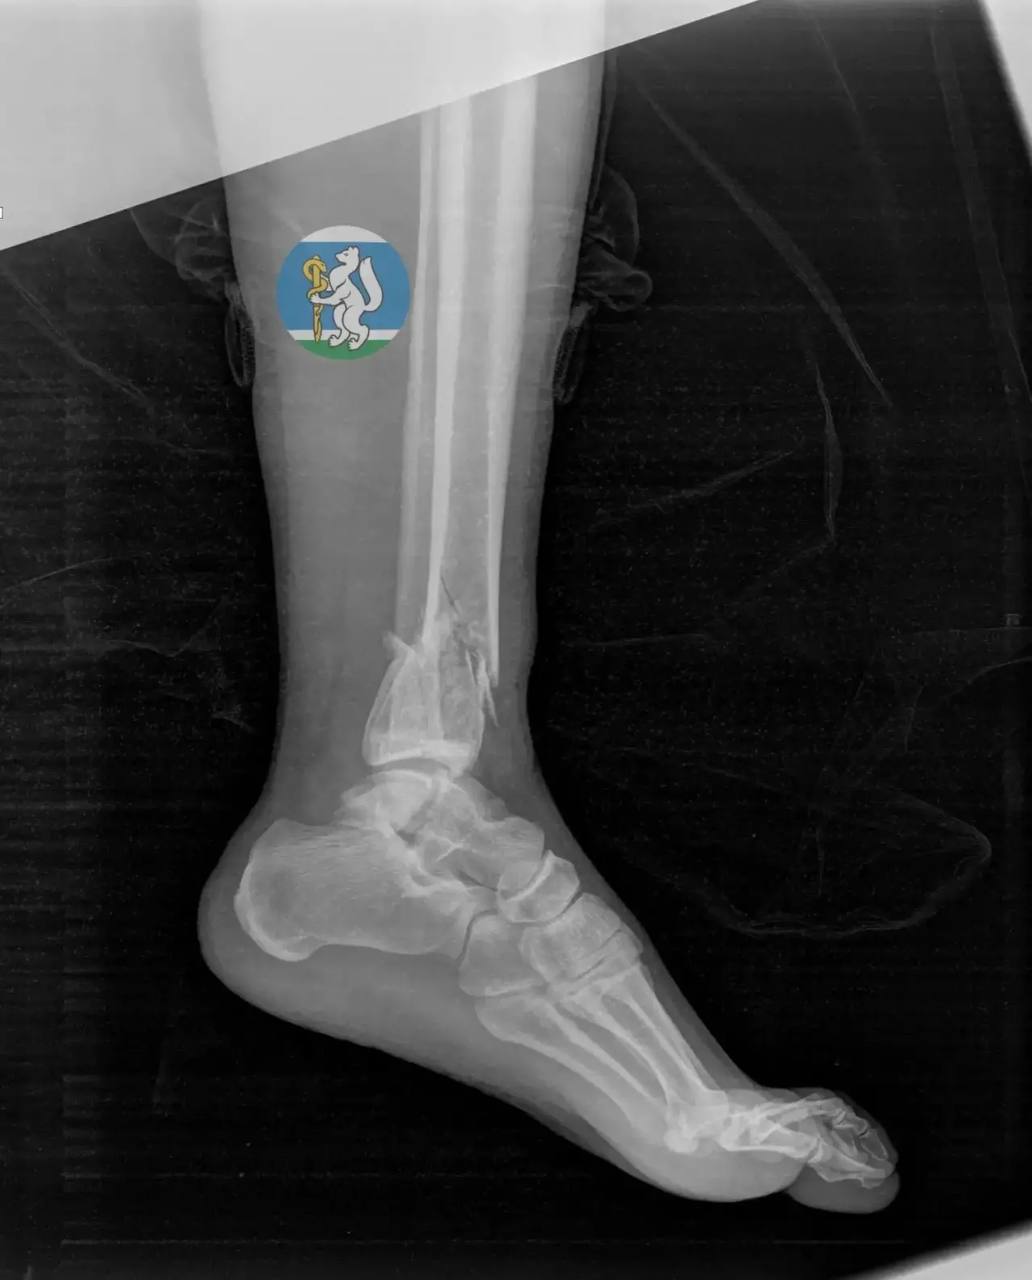

36-летняя жительница Екатеринбурга мыла окна на седьмом этаже и сорвалась вниз. С множественными переломами таза и позвоночника, открытыми переломами ног и тяжелой черепно-мозговой травмой ее доставили в Городскую больницу №36.

Большинство пациентов с такими повреждениями не выживают, но бригада хирургов, травматологов, нейрохирурга и реаниматолога несколько часов боролась за ее жизнь. Спустя месяц после серии сложнейших операций и реабилитации женщину выписали. Сейчас она восстанавливается дома.